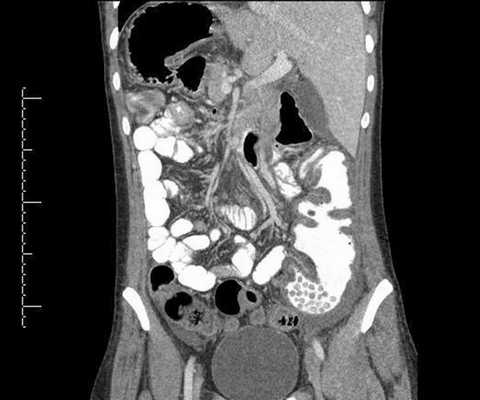

рис. 1-3 По данным МСКТ органов брюшной полости с в/в контрастированием: признаки объёмного образования на уровне мезогастрия (среднего этажа брюшной полости), связанное со стенкой тонкой кишки (дивертикул подвздошной кишки?).

Клинический диагноз:

Основной: Дивертикул подвздошной кишки.

Осложнения: перфорация дивертикула подвздошной кишки. Абсцесс брюшной полости.

Пациентка оперирована в плановом порядке в объеме лапароскопически-ассистированной резекции тонкой кишки. Лапароскопическойхолецистэктомии. Аппендектомии. Энтероэнтеростомии. Дренирования брюшной полости.

При проведении операции у пациентки было выявлено объемное образование, расположенное в мезогастрии с вовлечением стенки тощей кишки на нескольких участках. При вскрытии данного образования было выявлено наличие инородного тела (марлевая салфетка).

Из данного клинического случая можно сделать вывод:

для диагностики инородного тела крайне важным является сбор анамнеза с указанием предшествующей хирургической операции. При подозрении на наличие у пациента инородного тела МСКТ позволяет визуализировать в образовании пузырьки газа диаметром от 1,5 мм, оценить степень изменений в окружающей жировой клетчатке, взаимоотношение инородного тела с прилежащими органами, косвенно оценить наличие кровотока в подозрительном образовании.